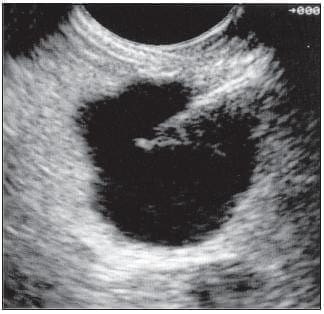

FIGURA 19. Se muestra un quiste en el cuerpo del páncreas que está siendo puncionado para estudio del líquido.

La ecoendoscopia permite distinguir cada uno de estos tumores según sus características endosonográficas (figura 19) y con la punción (63) se puede obtener material para estudio del contenido líquido, no sólo de sus marcadores bioquímicos sino de sus marcadores tumorales; el antígeno carcinoembrionario es el principal de ellos, el cual nos permite determinar si la lesión es maligna o tiene un potencial maligno.